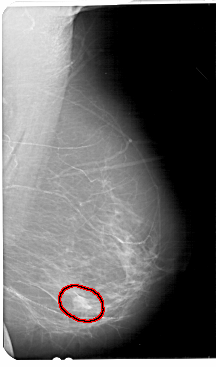

A_1681_1.RIGHT_MLO

RIGHT_MLO LINES 5491 PIXELS_PER_LINE 3226 BITS_PER_PIXEL 12 RESOLUTION 43.5 OVERLAY

FILE: A_1681_1.RIGHT_MLO.OVERLAY

TOTAL_ABNORMALITIES 1

ABNORMALITY 1

LESION_TYPE MASS SHAPE ROUND MARGINS ILL_DEFINED

ASSESSMENT 4

SUBTLETY 3

PATHOLOGY BENIGN

TOTAL_OUTLINES 1

BOUNDARY